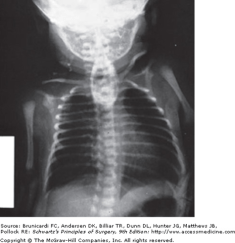

Type C esophageal atresia with tracheoesophageal fistula. Note the catheter coiled in the upper pouch and the presence of gas below the diaphragm, which confirms the presence of the tracheoesophageal fistula.

The diagnosis of EA is confirmed by the inability to pass an orogastric tube into the stomach (Fig. 39-10). The dilated upper pouch occasionally may be seen on a plain chest radiograph. If a soft feeding tube is used, the tube will coil in the upper pouch, which provides further diagnostic certainty. An important alternative diagnosis that must be considered when an orogastric tube does not enter the stomach is that of an esophageal perforation. This problem can occur in infants after traumatic insertion of a nasogastric or orogastric tube. In this instance, the perforation classically occurs at the level of the piriform sinus, and a false passage is created that prevents the tube from entering the stomach. Whenever there is any diagnostic uncertainty, a contrast study can confirm the diagnosis of EA and occasionally document the TEF; however, the obvious risks of aspiration associated with an undrained blind pouch cannot be overstated. The presence of a TEF can be demonstrated clinically by the finding of air in the GI tract. This can be proven at the bedside by percussion of the abdomen and confirmed by plain abdominal radiograph. Occasionally, a diagnosis of EA-TEF can be suspected prenatally on ultrasonographic evaluation. Typical features include failure to visualize the stomach and the presence of polyhydramnios. These findings reflect the absence of efficient swallowing by the fetus.